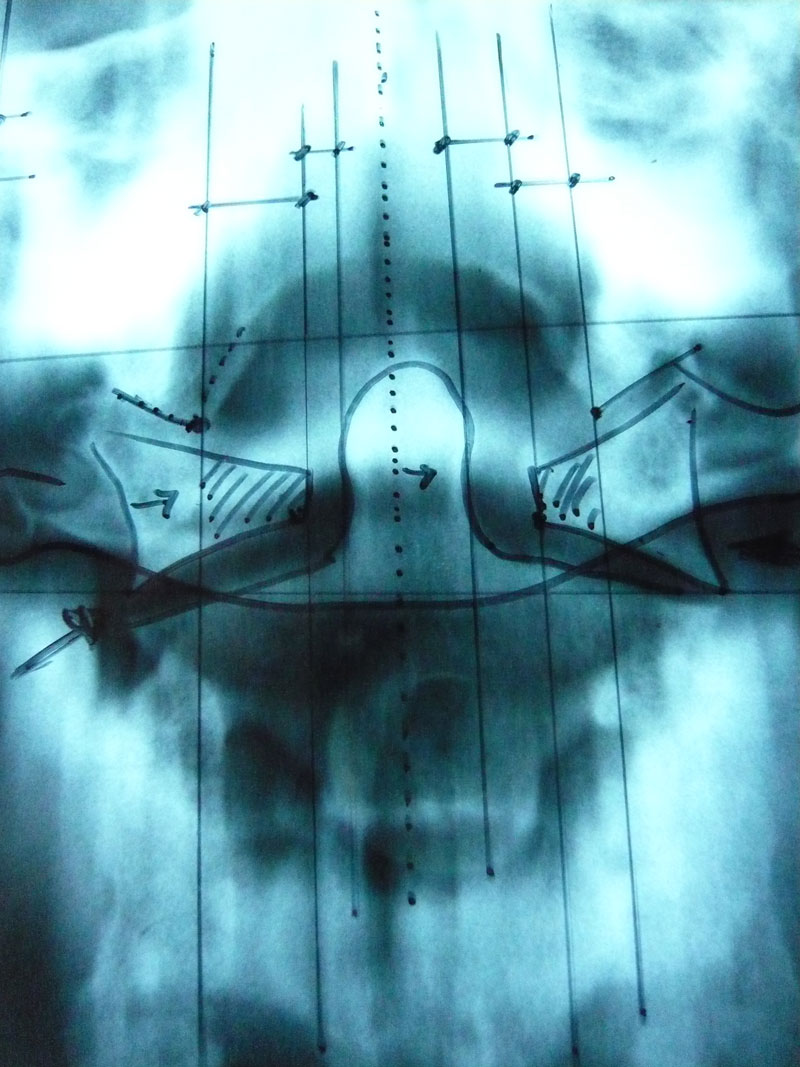

Neben der gründlichen klinischen Untersuchung des Patienten muss die Atlasstellung grundsätzlich auch röntgenologisch erfasst werden, da die atlantooccipitalen Gelenkflächen von außen nicht ertastet werden können. In manchen Fällen ist zusätzlich eine Zonographie des craniocervicalen Übergangs erforderlich – eine Untersuchungsmethode, die leider nur von wenigen Radiologen sicher beherrscht wird (z.B. Radiologische Praxis Memmingen, RZM Radiologisches Zentrum München-Pasing für CT-Aufnahmen).

Für spezielle Fragestellungen sind auch Bewegungsaufnahmen der HWS erforderlich, die nach dem Mobilitätsdiagramm nach ARLEN ausgewertet werden. Die diesbezüglichen wissenschaftlichen Veröffentlichungen von A. ARLEN et al sind in Fachkreisen stark beachtet worden.

Zur Beurteilung des gesamten atlanto-occipitalen Bandapparates, des Dens-Kapselapparates, der Lig. alaria, der Lig. transvers. atlantis usw. werden gegebenenfalls auch bildgebende Funktionsanalysen durchgeführt und – als sicherlich beste Methode – die im neuen Lehrbuch für Neurochirurgie im Kap. 9.2 empfohlene bildgebende Diagnostik des craniozervikalen Übergangs eine komplette funktionelle kernspintomographische Darstellung des gesamten Band-Kapselapparates in mehreren Bewegungseinstellungen. Diese Untersuchung entspricht dem neuesten Stand der medizinischen Technik. Sie wird u.a. in 85609 Aschheim bei München von Herrn Dr. med. Andreas Förg durchgeführt.